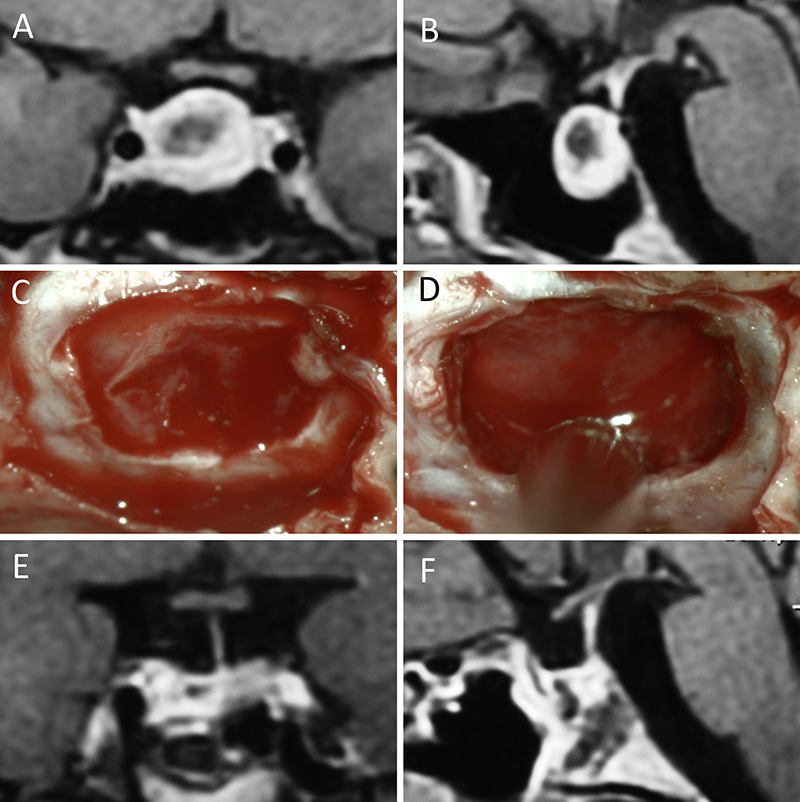

Figura 1: Macroadenoma no funcionante en mujer de 65 año s. Se decidió la cirugía tras evidenciarse crecimiento en los controles. Evolucionó favorablemente desde el punto de vista clínico-radiológico. A-B: RM preoperatoria; C-D: intraoperatorio; E-F: RM postoperatoria.

Figura 2: Macroadenoma no funcionante en mujer de 31 años. La paciente presentó en el preoperatorio déficit visual que mejoró tras la cirugía. A-B: RM preoperatoria; C-D: intraoperatorio; E-F: RM postoperatoria.